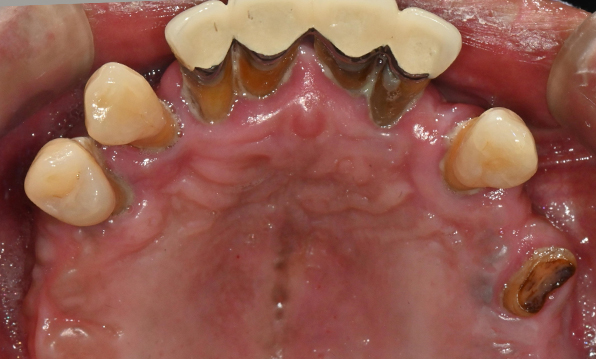

Before & After

| Before | After |